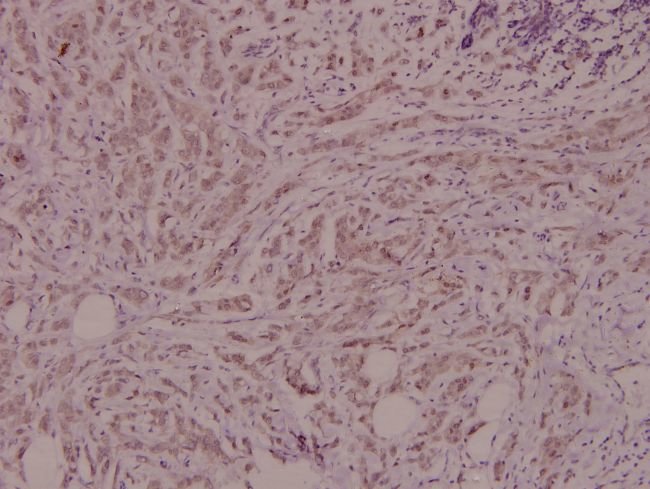

Invitrogen™ IL4R Polyclonal Antibody

Brand:  Invitrogen™ PA536522

This antibody detects endogenous protein at a molecular weight of 88 kDa. Purity is >95% by SDS-PAGE.

Immunohistochemistry (Paraffin), Western Blot

Synthetic peptide corresponding to amino acids 220-265 of human IL-4R alpha.

Human